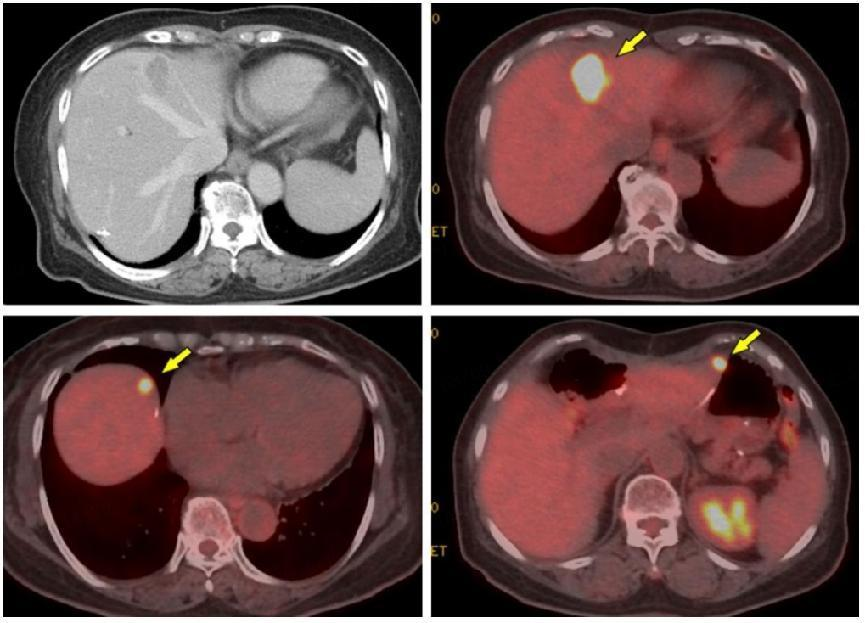

T-DXd治疗后观察到CEA再次迅速下降(图3),影像学疗效评价PR(根据RECIST v1.1)。CT和FDG-PET复查结果显示肝脏S4孤立性病变,在T-DXd治疗19个月后仍存在(图7)。

图7:三线治疗19个月后影像学检查